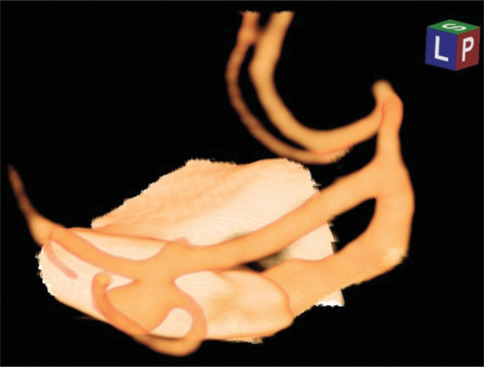

Remote cerebral vasospasm following elective clipping of middle cerebral artery bifurcation-A1 aneurysms: A correspondence and review of putative pathophysiological mechanisms.

选择性切断大脑中动脉分叉a1动脉瘤后的远端脑血管痉挛:对假定病理生理机制的对应和回顾